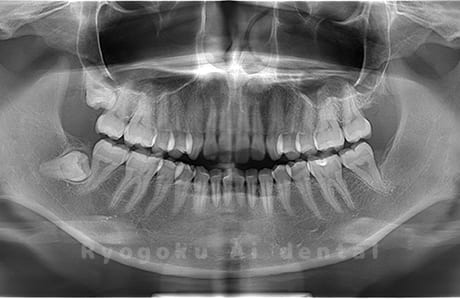

Case04

- 原因

- 上顎の親知らず、下顎の水平埋伏の親知らず

- 治療内容

- 上顎の親知らず、下顎の水平埋伏の親知らずを抜歯したケースです。

<リスク・副作用>

手術後は痛み、腫れ、痺れなどの副作用が生じる場合があります。